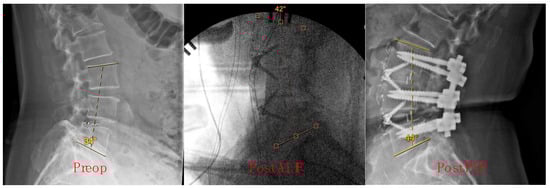

Measurements were conducted at three key time points: before ALIF in the standing position, post-ALIF in the supine position, and post-PSF in the prone position. These specific time points were chosen to capture the dynamic changes in lumbar lordosis throughout the surgical process, from preoperative baseline to immediate postoperative status. The choice of measurement technique was based on its widespread use in clinical practice and its established reliability in assessing spinal alignment [,,]. Additionally, the selected measurement points were consistent with standard protocols for evaluating lumbar lordosis in spinal surgery research []. Sample X-ray images illustrating the calculation of preop, post-ALIF, and post-PSF Cobb angles are shown in Figure 1.

Figure 1.

Cobb angle measurement at preop, post-ALIF, and post-PSF timepoints.